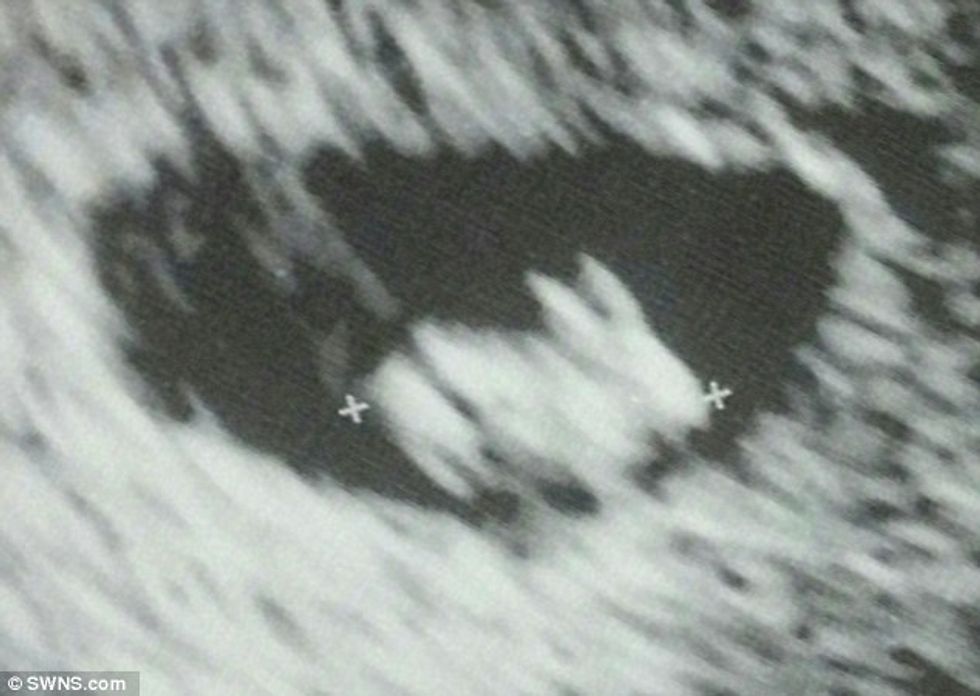

Fotografia bizare e ultrazërit, shfaqet një ‘lepur’ në vend të fëmijës (Foto)

Një nënë e ardhshme nga Florida e Shteteve të Bashkuara, është mahitur në rrjetin social Redit se mbanë në bark një lepur.

Shtatzëna 33-vjeçare, që nuk ka dashur të identifikohet, e ka postuar imazhin ku shihet brejtësi veshgjatë që ka katër këmbë, transmeton Telegrafi.

“Shkova për herë të parë për të bërë ultrazërin dhe doli se do ta lindi një lepur”, ka shkruar ajo përbri fotografisë.

Mësohet se fetusi që është në javën e shtatë, ka një formë normale dhe është i shëndoshë, ndërsa kjo pamje komike që është zënë rastësisht nga njëri kënd. /Telegrafi/